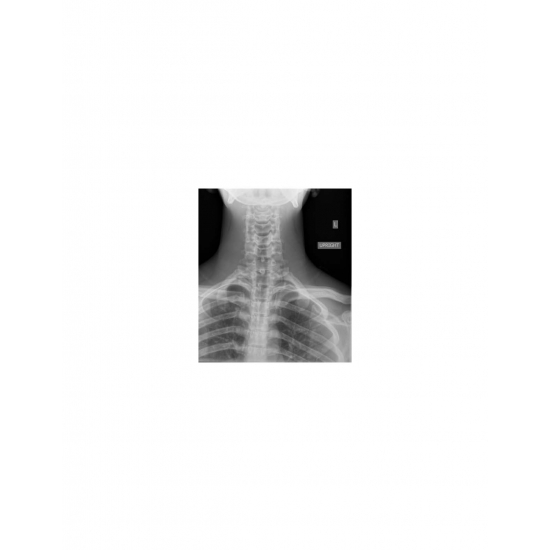

| Odynophagia In A Collegiate Baseball Player - Page #3 | |||